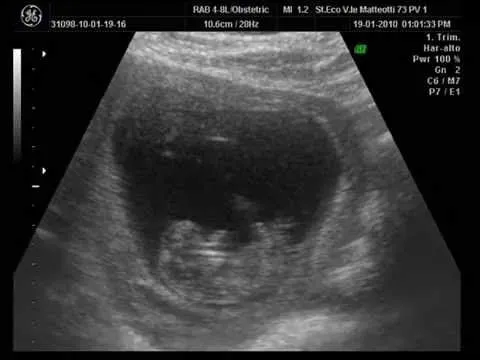

ecografia de mi bebe..."mi primogenito" 2 meses y 1/2 - YouTube